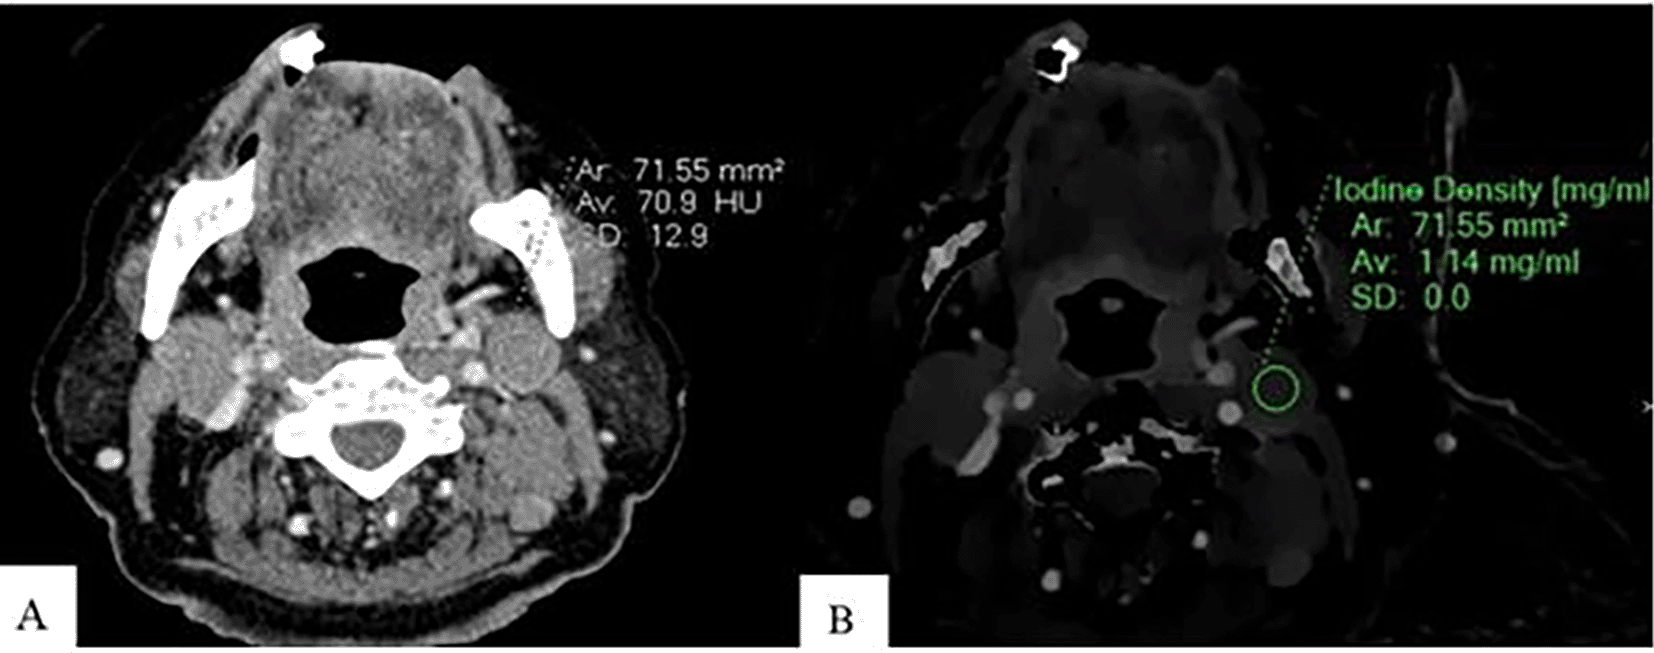

Spectral post-processing workstation (IntelliSpace Portal v11, Philips Healthcare, Netherlands) was used togenerateID and contrast-enhanced images (Figures 1, 2, and 3).

An Axial CT image of a patient with lymphoma shows CEAV measurement (70.9 HU) of the enlarged lymph node at left cervical level IIA (A). An ID measurement (1.14 mg/ml) of this lymph node at the same CT level (B).